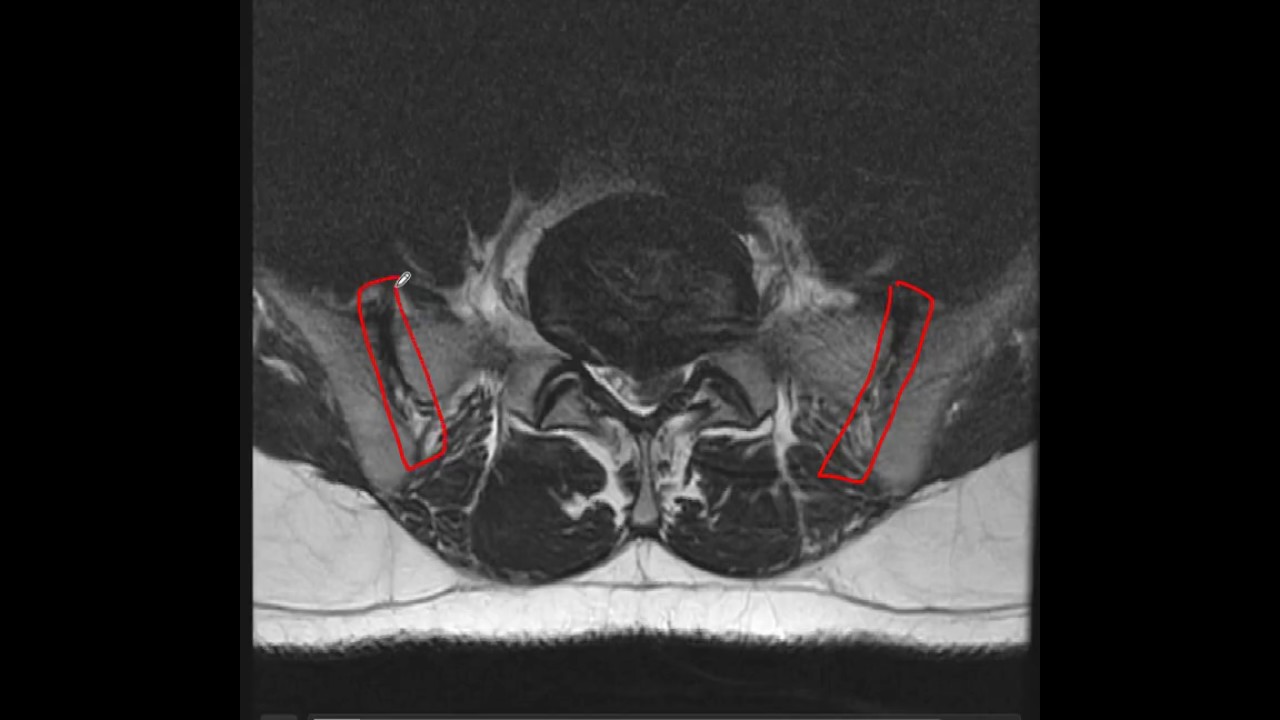

con la apis Espinosa por medio de la lámina es muy común de que ustedes escuchen la palabra laminectomía cuando hay una hernia y se necesita entrar al conducto medular se hace lo que se llama laminectomía se corta la lámina y se puede ingresar de esta manera al conducto medular si lo miramos de lateral tenemos lo mismo hacia adelante el cuerpo hacia atrás hacia lateral la pis transversa y hacia atrás la pis Espinosa y acá vemos el pedículo y acá la lámina la pis transversa naciendo del pedículo hacia delante y de la lámina hacia atrás esto